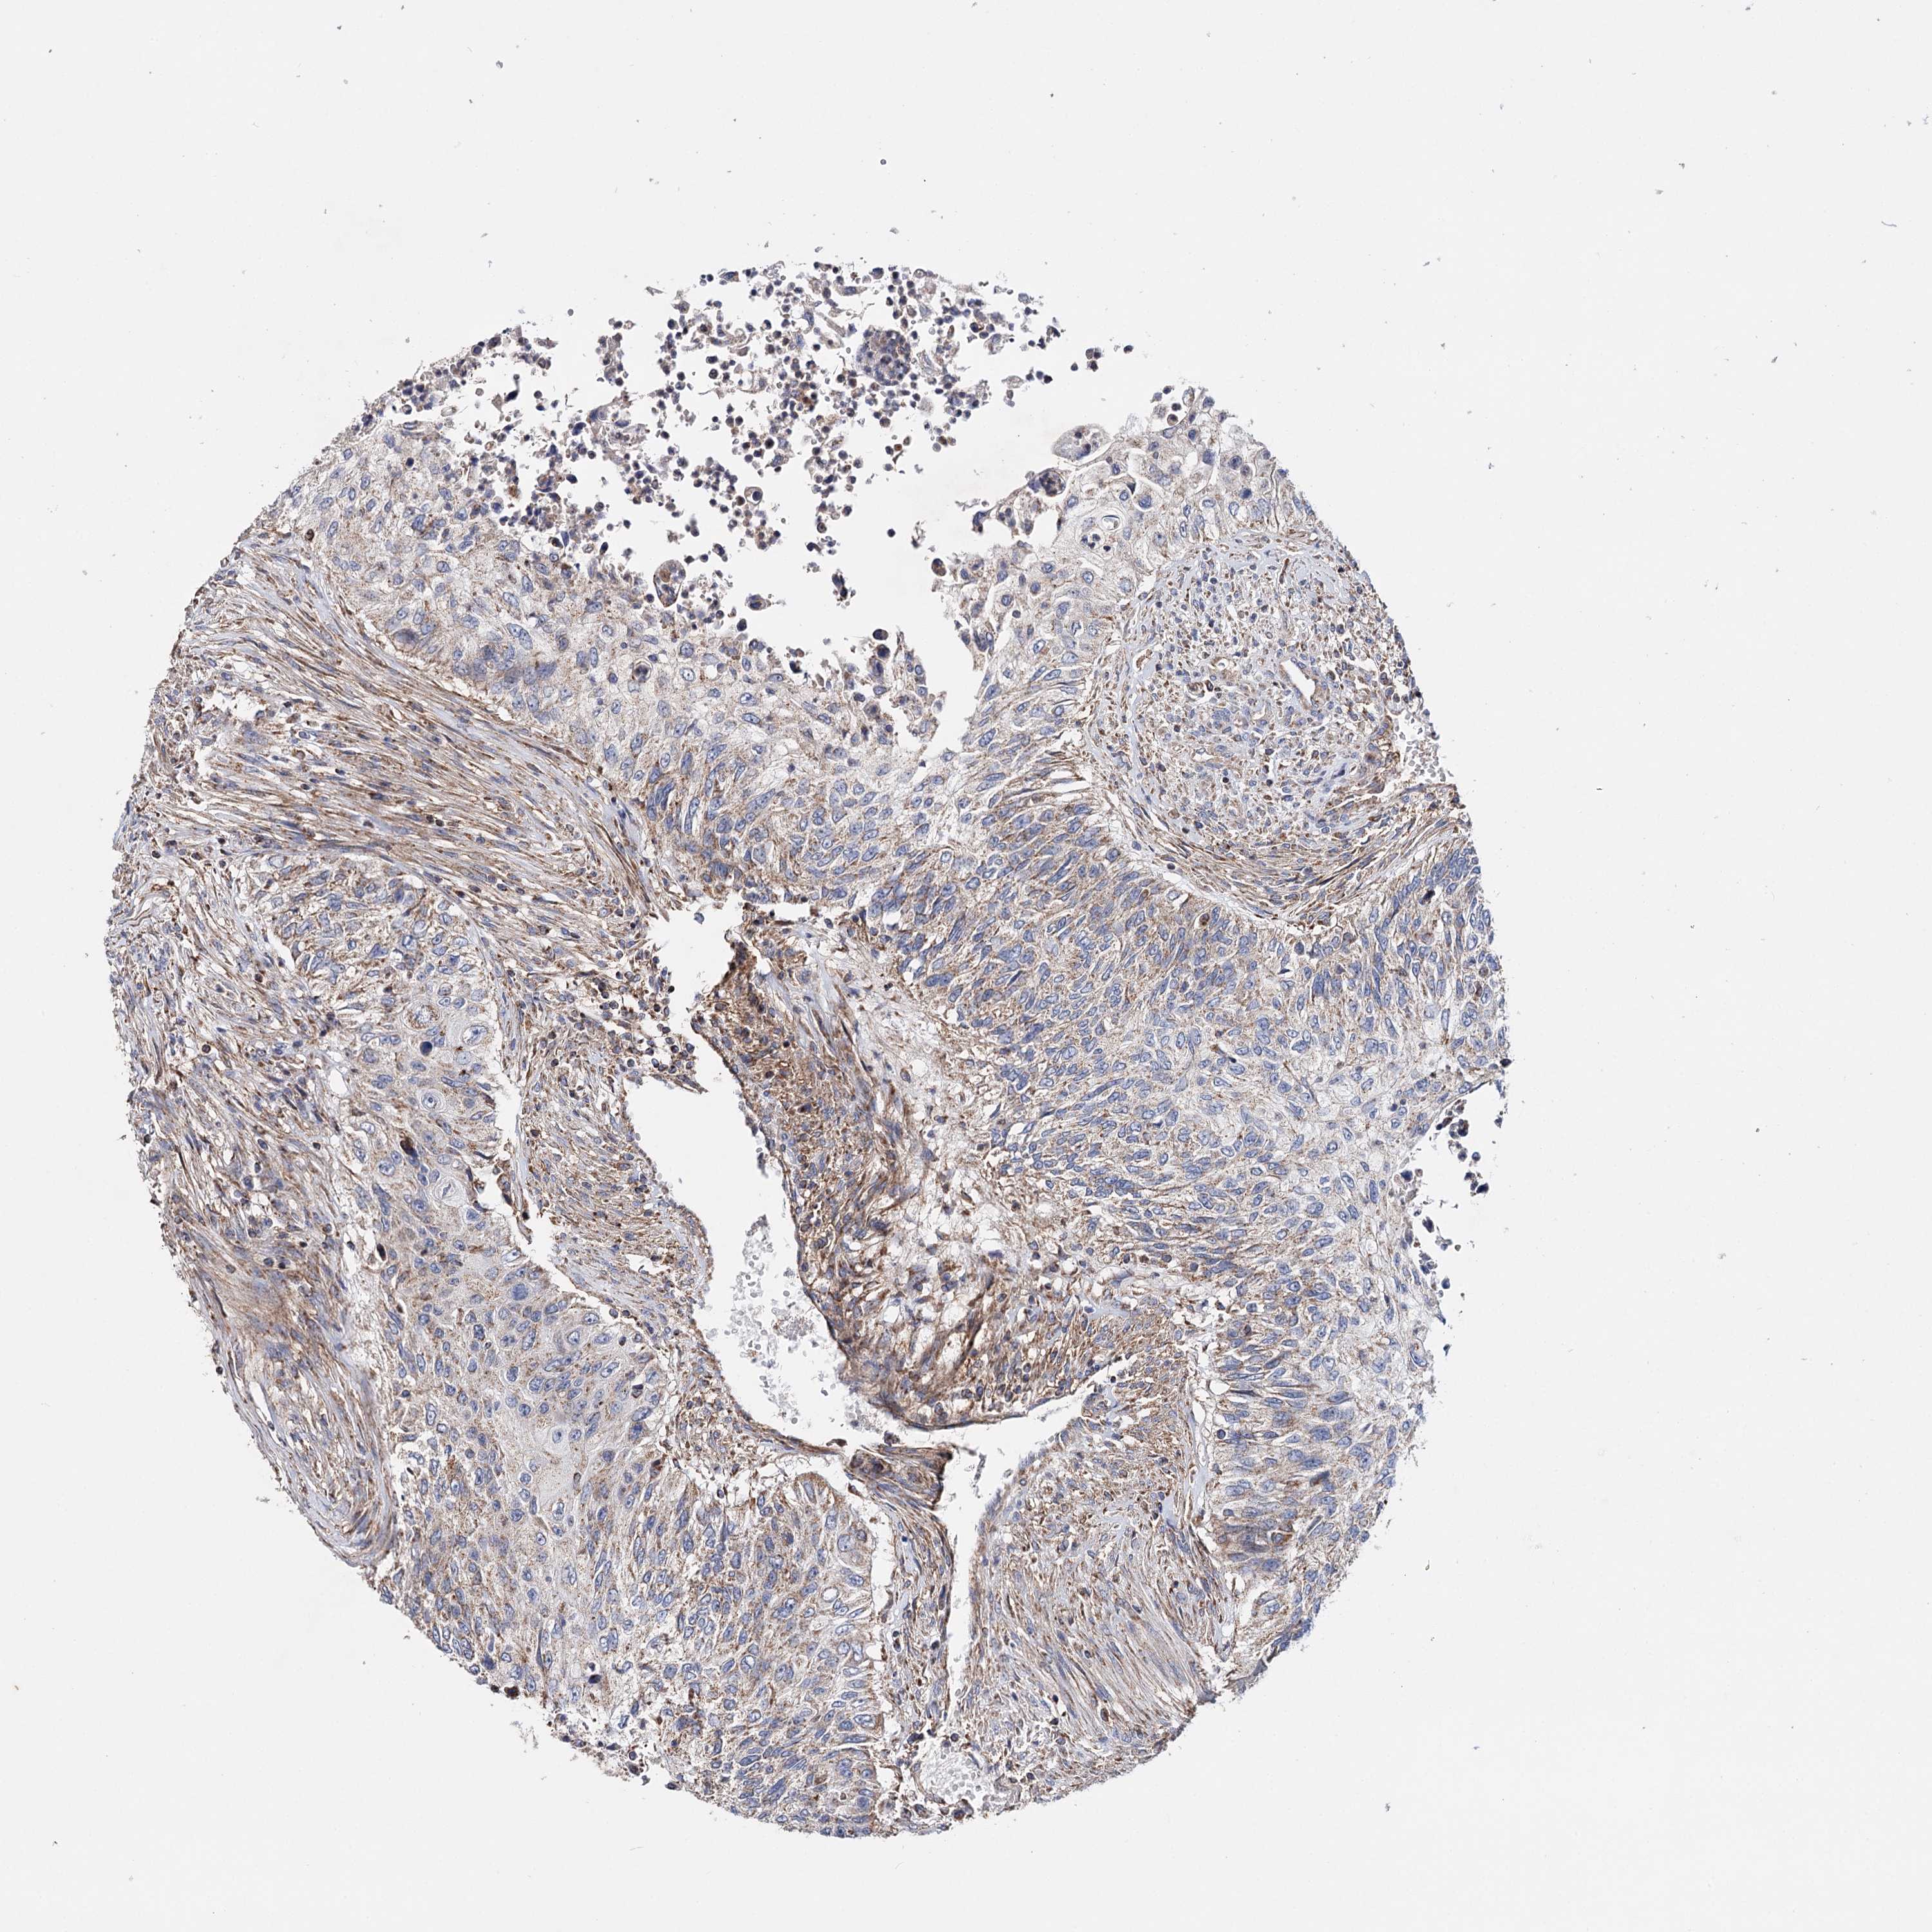

UROTHELIAL CANCER - Protein expressioni

A mouse-over function shows sample information and annotation data. Click on an image to view it in a full screen mode. Samples can be filtered based on level of antibody staining by selecting one or several of the following categories: high, medium, low and not detected. The assay and annotation is described here.

Note that samples used for immunohistochemistry by the Human Protein Atlas do not correspond to samples in the TCGA dataset.

Antibody stainingi

Antibody staining in the annotated cell types in the current human tissue is reported as not detected, low, medium, or high, based on conventional immunohistochemistry profiling in selected tissues. This score is based on the combination of the staining intensity and fraction of stained cells.

Each image is clickable and will lead to virtual microscopy that enables deeper exploration of all samples and also displays staining intensity scores, fraction scores and subcellular localization as well as patient and tissue information for each sample.

Antibody HPA037786

Antibody HPA038034

Antibody HPA038867

Antibody HPA038868

Staining

High

Medium

Low

Not detected

Intensity

Strong

Moderate

Weak

Negative

Quantity

>75%

75%-25%

<25%

None

Location

Nuclear

Cytoplasmic/membranous

Cytoplasmic/membranous,nuclear

Urothelial carcinoma, High grade

Urothelial carcinoma, Low grade

Urothelial carcinoma, NOS